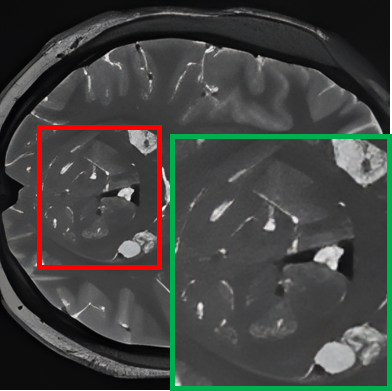

Table II provides a visual comparison of 7T-like MRI generated by various State-Of-The-Art (SOTA) SR methods using 1.5T MRI as input. The compared methods include ESRGAN [43], SR3 [26], and our proposed baseline (teacher) model. To facilitate a focused and intuitive assessment, the cerebellar region, known for its intricate structure and HR requirements, is specifically selected for comparison. To comprehensively evaluate the methods, T1w and T2w slices from both the axial and coronal planes are displayed in an alternating interleaved format, which highlights each method’s effectiveness across distinct anatomical views and tissue contrasts, allowing for a clearer assessment of their ability to capture fine structural details. The comparison reveals that ESRGAN enhances the resolution but introduces significant artifacts, where unnatural patterns distort the anatomical structures. While it provides some sharpening, the output deviates substantially from the ground truth. SR3, on the other hand, prioritizes smoothness, leading to blurred outputs that fail to recover fine details and textures, which results in a loss of critical anatomical information. In contrast, the proposed teacher model excels in preserving fine structural details and reconstructs intricate anatomical features without introducing artefacts or excessive blurring, demonstrating superior performance compared to ESRGAN and SR3 in both visual quality and alignment with the 7T ground truth. Additionally, the comparison highlights a consistent discrepancy in SR performance between T1w and T2w images. T2w images generally exhibit inferior reconstruction quality, which can be attributed to their inherently lower SNR and higher susceptibility to magnetic field inhomogeneities. These characteristics pose significant challenges for SR models, making accurate reconstruction more difficult. Despite these challenges, our proposed model consistently outperforms ESRGAN and SR3, delivering superior results for both T1w and T2w imaging.

TABLE II: Qualitative visualization comparison with SOTA models

Input (1.5T) Ground Truth (7T) ESRGAN SR3 Ours (Teacher)

T1w

[Uncaptioned image] [Uncaptioned image] [Uncaptioned image] [Uncaptioned image] [Uncaptioned image]

T2w